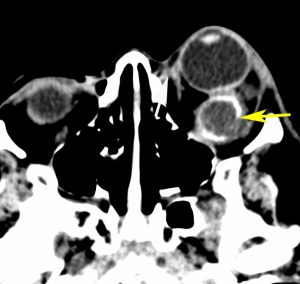

左が16歳,右が23歳の時のMRI画像です。太く見えた視神経が,大きな塊となりました。ガドリニウム増強で,腫瘍の内部が部分的に増強されます。眼球が突出して目を閉じることができず,むき出しになりました。8歳から23歳まで,15年間かかってゆっくり大きくなったし眼窩内神経膠腫です。

CTでは高度の眼球突出があり,腫瘍の辺縁が石灰化していて視神経鞘を含めて極めて硬い線維性腫瘍となっていることがわかります。T2強調画像では高信号で腫瘍が増大傾向を示し,一部が嚢胞性であることがわかります。下のT1増強像では腫瘍の中心部分に増強される増殖部位があることがわかります。

この腫瘍には放射線治療はできませんし,化学療法も効きません。手術で摘出するのですが,視力が既にないので,整容的に,左眼球を温存すること,瞼と眼球運動を温存することが目的となります。